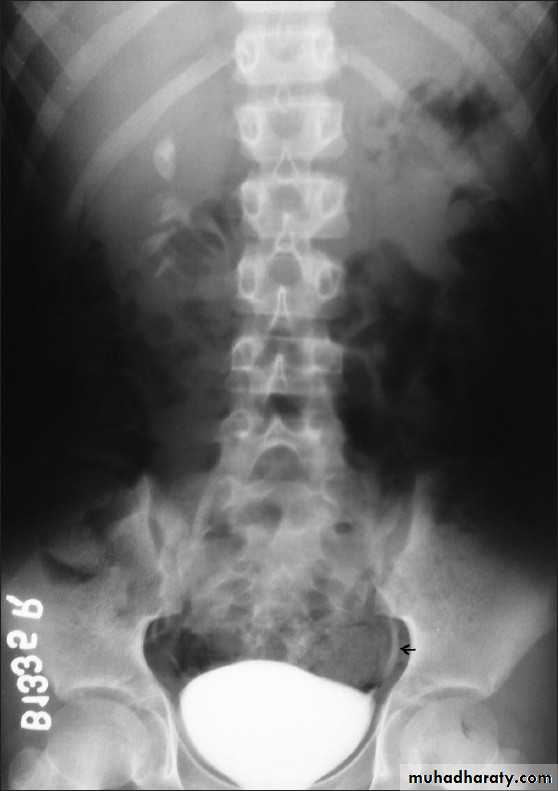

*Ectopic left kidney:-ureter is short (small arrow)

*Phlebolith (arrow):-round lucent centre,,it represents calcified thrombus in pelvic vein.